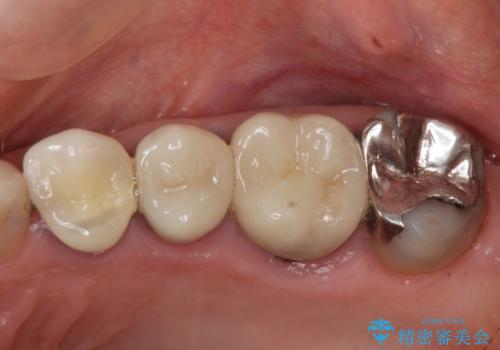

- 97.9万円(インプラント×2・アバットメント×2・仮歯×2・ジルコニアクラウン×2・骨造成)費用は治療当時の料金となります